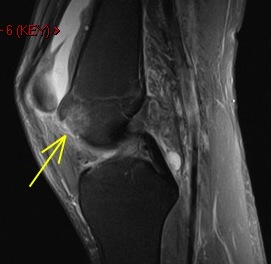

36 y/o was running and struck by car

Osteochondral fracture of the medial femoral trochlea. Notice the displaced chondral fragment behind the lateral femoral condyle interposed between the condyle and the posterior lateral capsule. Moral of the story – if you see an acute defect, look for the fragment.

Osteochondral fracture femur with displaced fragment